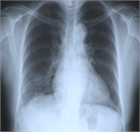

1. Q熱コクシエラ肺炎症例の胸部X線所見は典型例では多発性の肺野斑状影を呈する。